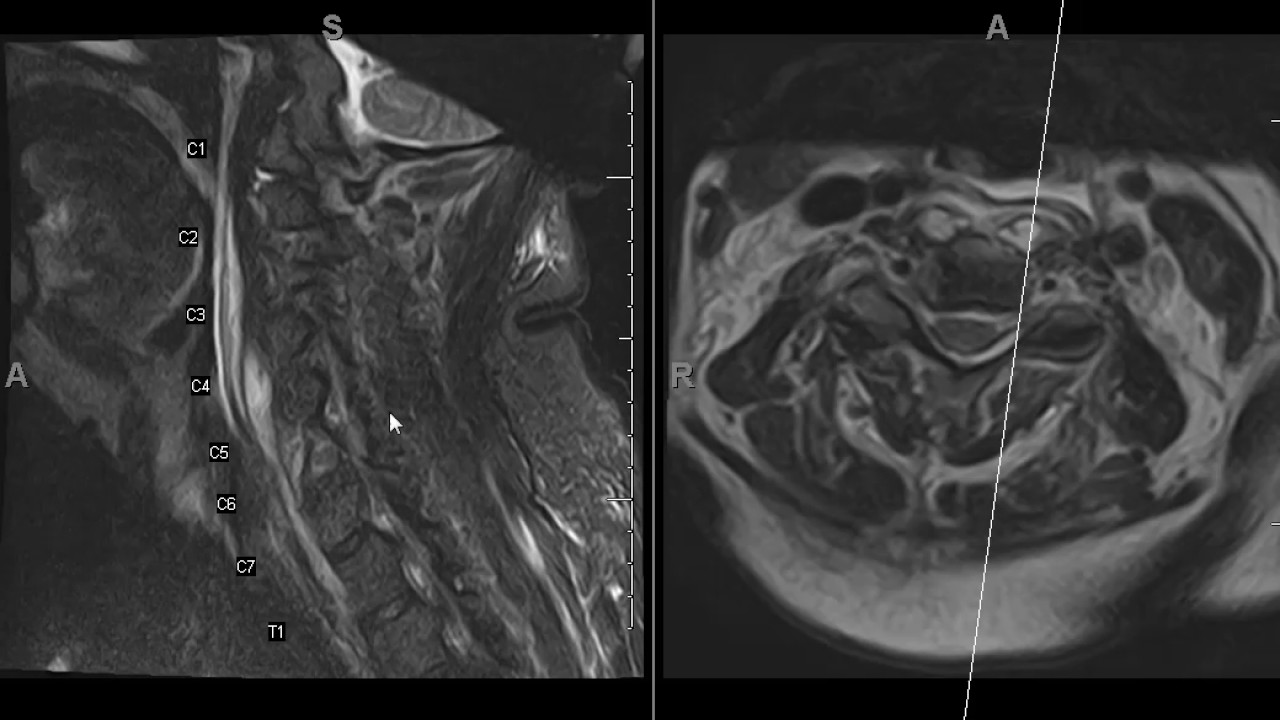

BEFORE WATCHING: Take the quiz here: https://ctisus.com/learning/quiz/2024/05 This video has answers & explanations Check out the apple App Store for CTisus apps https://tinyurl.com/y2pyjzhv Keep in Touch at: Facebook:   / ctisus   Twitter:   / ctisus   Instagram:   / ctisus_radiology   TikTok:   / ctisus   LinkedIn:   / ctisus   CTisus.com is an informational and educational radiological resource dedicated to CT scanning. Founded by Elliot K. Fishman, M.D. The website provides the latest information regarding radiology technology and 3D imaging. It features a library of content, including lectures and case studies, as well as medical illustrations and other radiology resources.